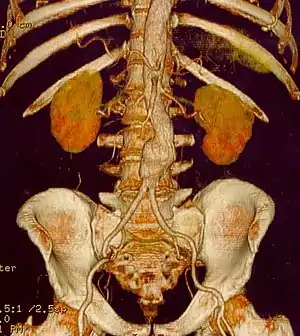

CT reconstruction image of an abdominal aortic aneurysm

The risk of rupture of an AAA is related to its diameter; once the aneurysm reaches about 5 cm, the yearly risk of rupture may exceed the risks of surgical repair for an average-risk patient. Rupture risk is also related to shape; so-called "fusiform" (long) aneurysms are considered less rupture-prone than "saccular" (shorter, bulbous) aneurysms, the latter having more wall tension in a particular location in the aneurysm wall.[8]

Before rupture, an AAA may present as a large, pulsatile mass above the umbilicus. A bruit may be heard from the turbulent flow in the aneurysm. Unfortunately, however, rupture may be the first hint of AAA. Once an aneurysm has ruptured, it presents with classic symptoms of abdominal pain which is severe, constant, and radiating to the back.[8]

The diagnosis of an abdominal aortic aneurysm can be confirmed at the bedside by the use of ultrasound. Rupture may be indicated by the presence of free fluid in the abdomen. A contrast-enhanced abdominal CT scan is the best test to diagnose an AAA and guide treatment options.[9]